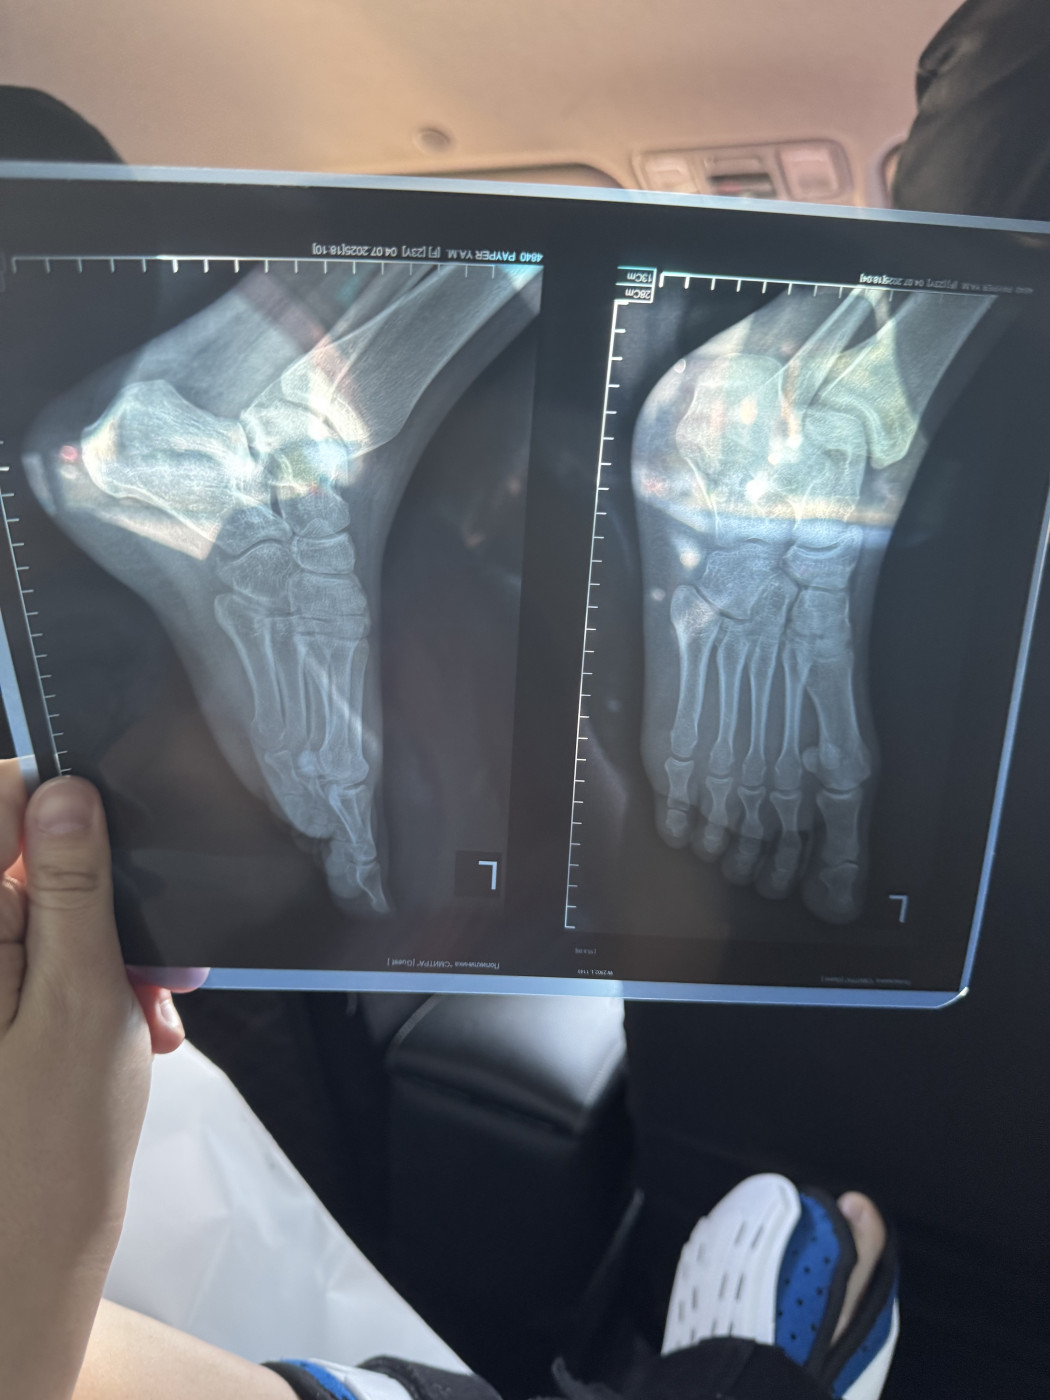

Перелом ноги   1 ответ

Здравствуйте. Диагноз: Закрытый перелом медиальной лодыжки со смещением отломков, перелом н/3

малоберцовой кости с незначительным смещением отломков и разрывом дистального

межберцового синдесмоза. Закрытый перелом заднего края большеберцовой кости без смещения в левом голеностопном суставе. Проведена операция. Какие последствия перелома и сроки восстановления? Особенно смещение малоберцовой кости которое осталось без изменений

26 июл 2025 11:55